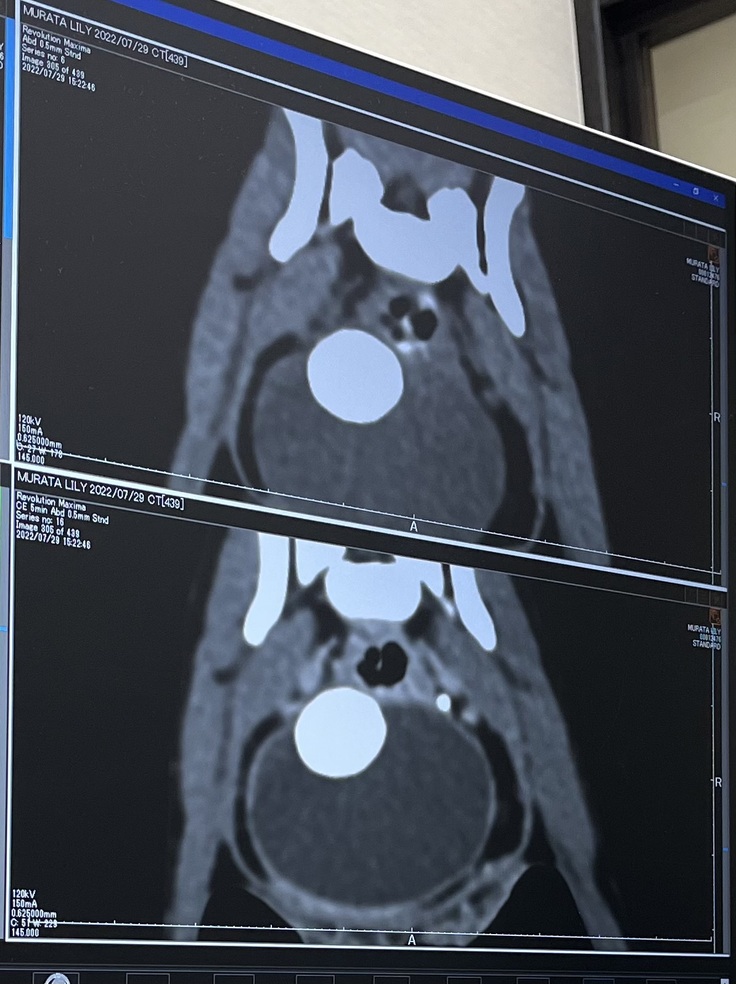

↓膀胱結石

↓門脈シャント血管(先生はこの画像でシャント血管が見えているみたいです)